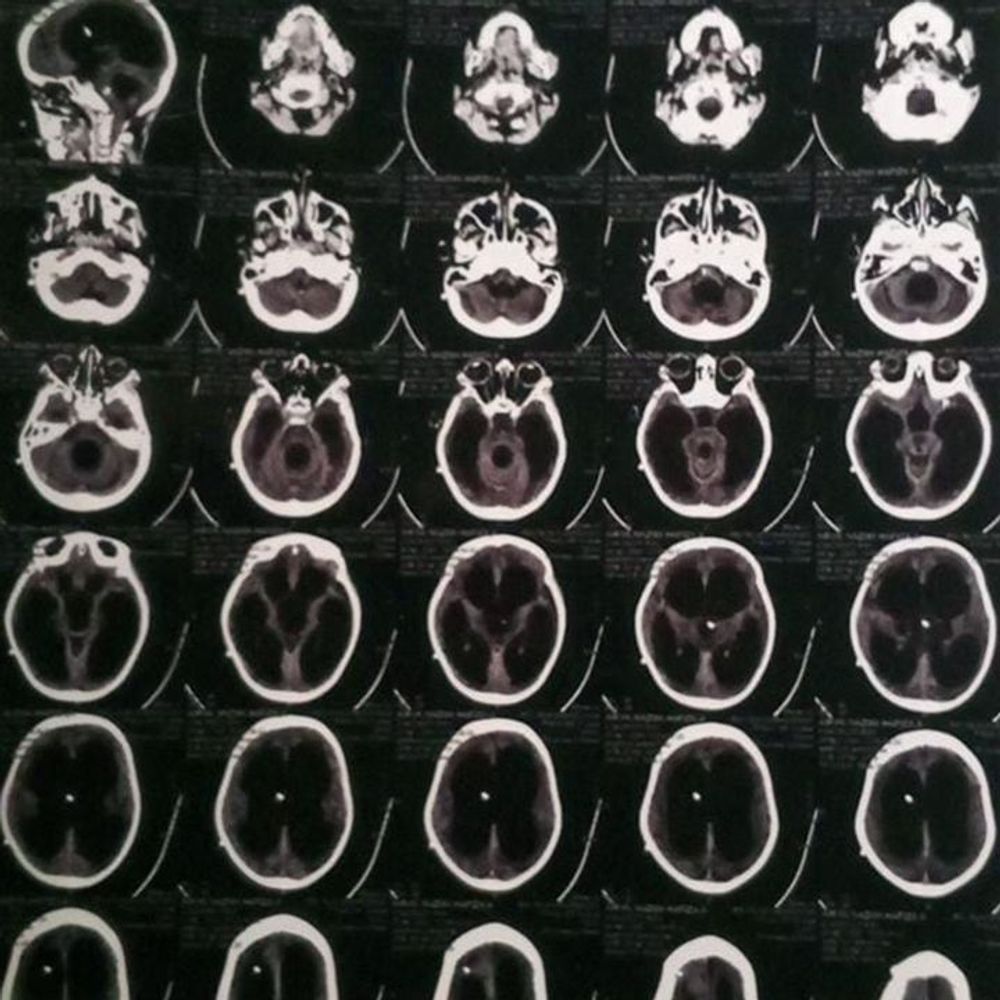

But in mid-2023, a persistent high fever changed everything. After repeated hospital visits and worsening symptoms, she was rushed to the ER with seizures and loss of consciousness. Doctors diagnosed her with TB meningitis, causing fluid buildup in her brain. She underwent urgent VP Shunt surgery to drain the fluid.

For 28 days, Airyn lay in a coma. Since then, her condition has been fragile. She suffers from malnutrition and requires frequent hospital visits, sometimes 9–10 times a month. When her shunt became blocked, she endured another major surgery to replace it. She now depends on ongoing therapies, monthly check-ups, and specialized care.